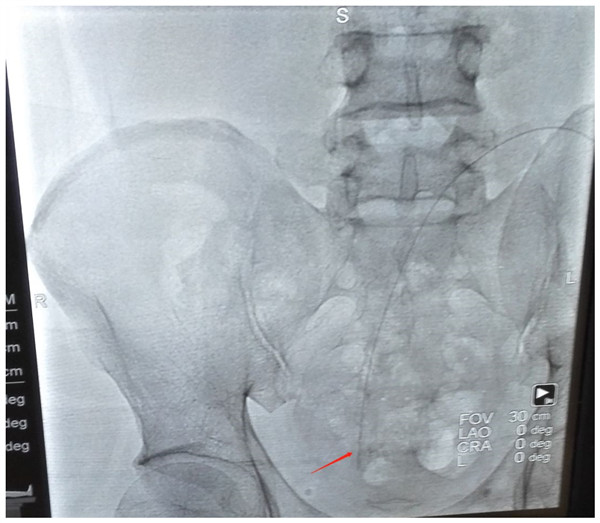

據(jù)了解患者周某,男,42歲,于2年前診斷為慢性腎功能不全尿毒癥期,應(yīng)用腹膜透析進(jìn)行腎臟替代治療?;颊哂?月14日因腹膜透析超濾減少收入腎內(nèi)科治療。腹部DR片示腹膜透析導(dǎo)管移位。

復(fù)位前圖片

此次經(jīng)中心醫(yī)院腎內(nèi)科劉濤主任與介入檢查中心負(fù)責(zé)人韓洪武主任討論研究決定在X光下導(dǎo)絲介入腹膜透析導(dǎo)管復(fù)位術(shù)。術(shù)前科室對(duì)該技術(shù)的可行性、技術(shù)難度及相關(guān)并發(fā)癥進(jìn)行了充分討論,詳細(xì)制定了治療方案。于2月19日下午兩個(gè)科室聯(lián)合為患者進(jìn)行了X光下導(dǎo)絲介入腹膜透析導(dǎo)管復(fù)位術(shù)。術(shù)畢行腹膜透析換液即超濾400毫升,復(fù)位成功。

復(fù)位后圖片